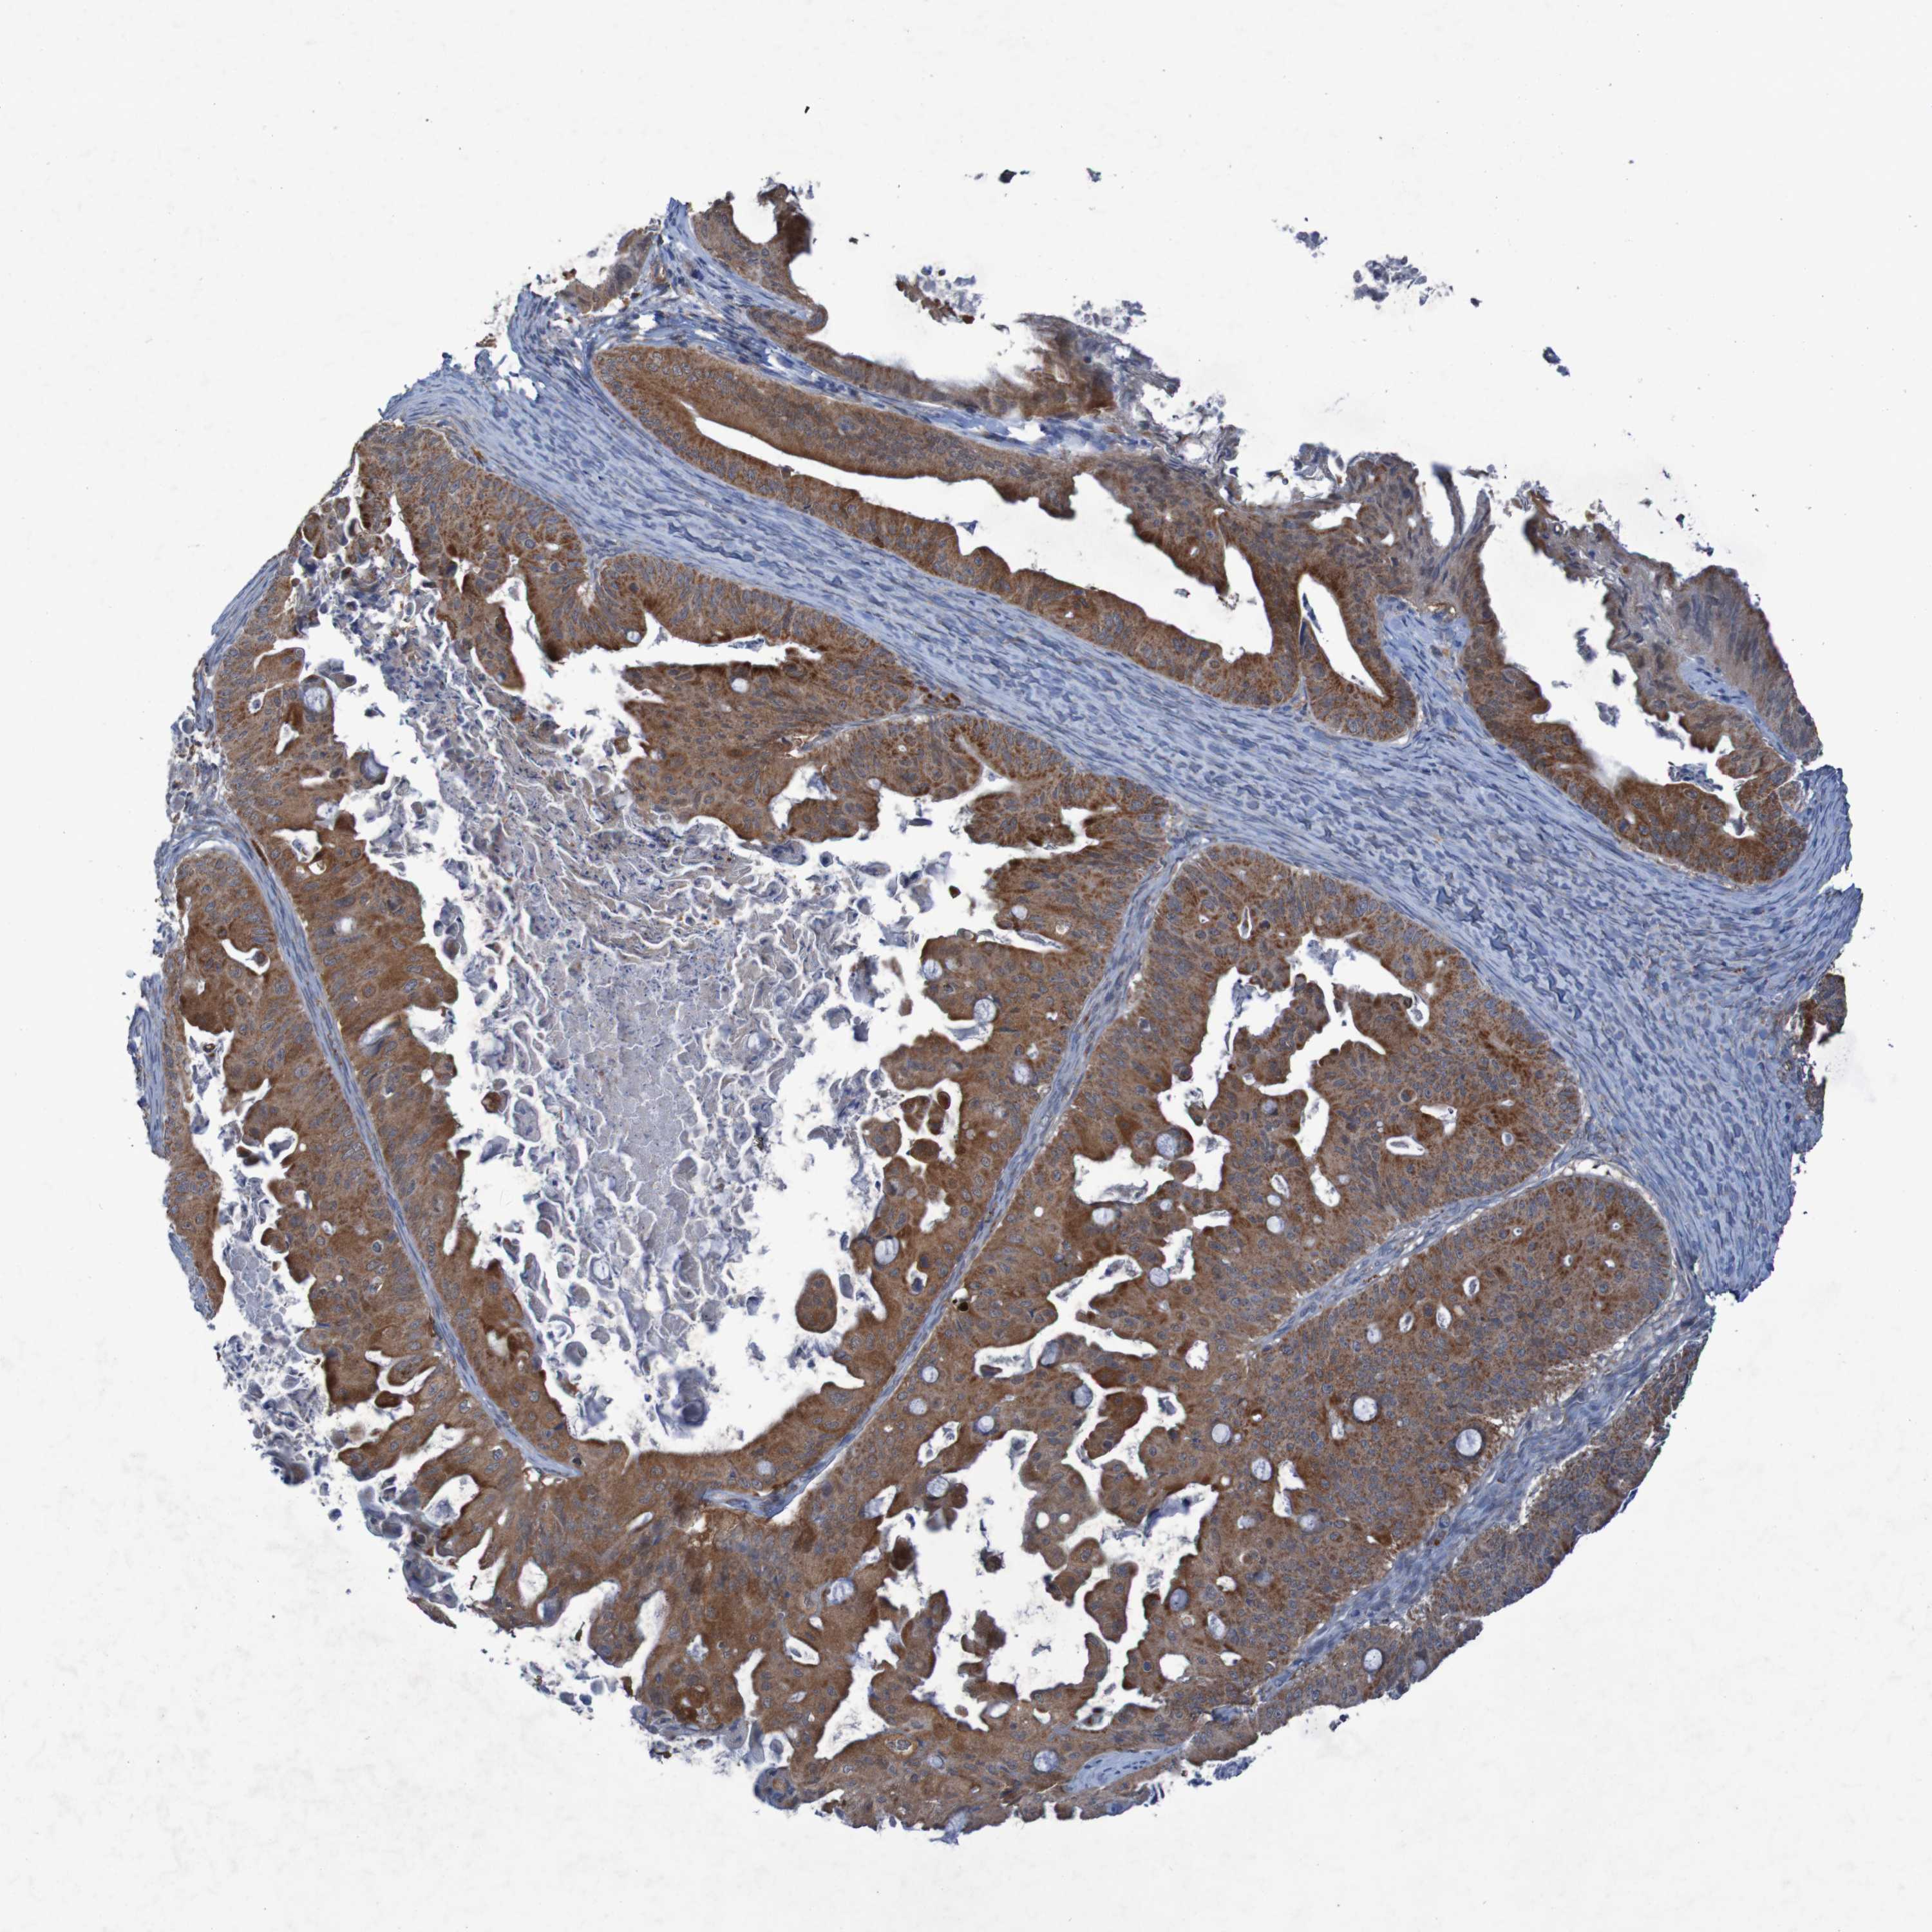

OVARIAN CANCER - Protein expressioni

A mouse-over function shows sample information and annotation data. Click on an image to view it in a full screen mode. Samples can be filtered based on level of antibody staining by selecting one or several of the following categories: high, medium, low and not detected. The assay and annotation is described here.

Note that samples used for immunohistochemistry by the Human Protein Atlas do not correspond to samples in the TCGA dataset.

Antibody stainingi

Antibody staining in the annotated cell types in the current human tissue is reported as not detected, low, medium, or high, based on conventional immunohistochemistry profiling in selected tissues. This score is based on the combination of the staining intensity and fraction of stained cells.

Each image is clickable and will lead to virtual microscopy that enables deeper exploration of all samples and also displays staining intensity scores, fraction scores and subcellular localization as well as patient and tissue information for each sample.

Antibody HPA010980

Antibody HPA011408

Staining

High

Medium

Low

Not detected

Intensity

Strong

Moderate

Weak

Negative

Quantity

>75%

75%-25%

<25%

None

Location

Nuclear

Cytoplasmic/membranous

Cytoplasmic/membranous,nuclear

Cystadenocarcinoma, serous, NOS

Carcinoma, endometroid

Cystadenocarcinoma, mucinous, NOS

Carcinoma, NOS